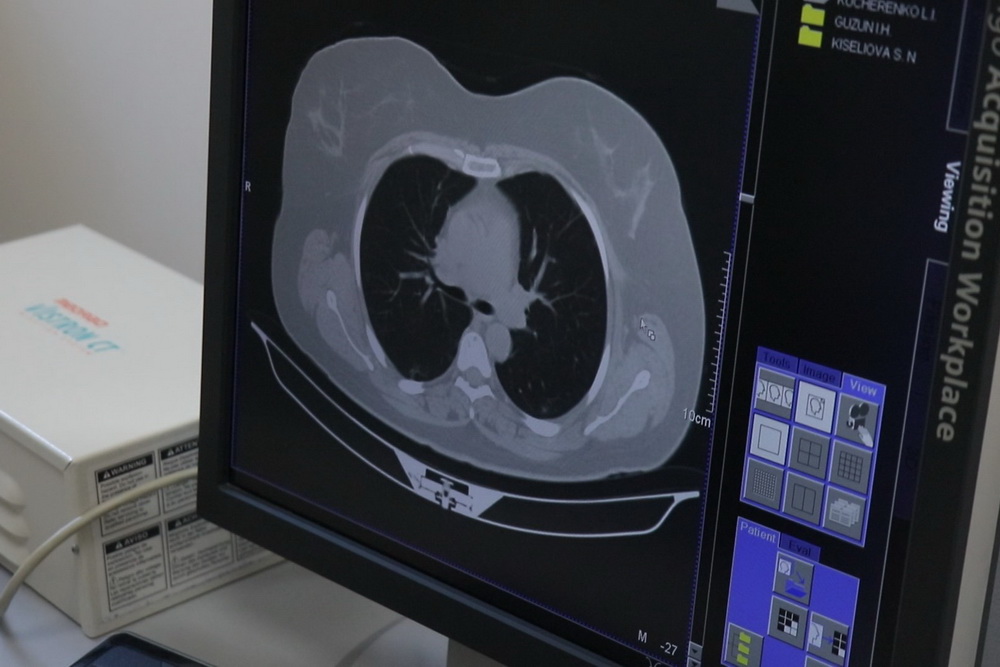

Дубоссары, 6 апреля. /Новости Приднестровья/. В дубоссарской Центральной районной больнице, на базе которой в течение года действует коронавирусный госпиталь, установили компьютерный томограф (КТ) и уже второй день проводят диагностические исследования пациентов из «красной зоны» медучреждения.

«Это современное оборудование, мы проводили на этом компьютерном томографе в госпитале инвалидов ВОВ исследования головного мозга, брюшной полости, грудной полости, сосудов, позвоночника. Большинство клинических задач, которые стояли перед нами, решали. Томограф в рабочем состоянии, к нему была докуплена новая рентгеновская трубка, так как предыдущая отработала 5 лет и с её помощью было выполнено более 1 200 000 снимков. А сейчас в день будем брать 15-20 пациентов. Пока врач проходит обучение», - рассказал врач-рентгенолог Республиканского госпиталя инвалидов ВОВ Павел Силецкий.

На компьютерном томографе в Дубоссарах со временем будут проводить диагностику большего количества пациентов, а также исследовать не только грудную клетку, но и другие области. В больнице будут принимать местных жителей, а также пациентов из Григориопольского и Рыбницкого районов.